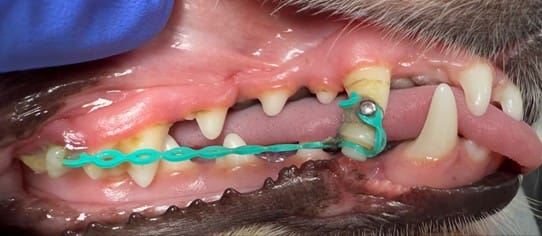

When a dog experiences facial traumaโwhether from a fall, bite wound, accident, or chewing something too hardโjaw fracture treatment for

Jaw Fracture Treatment for Dogs: When Surgery Is Needed Read Post ยป